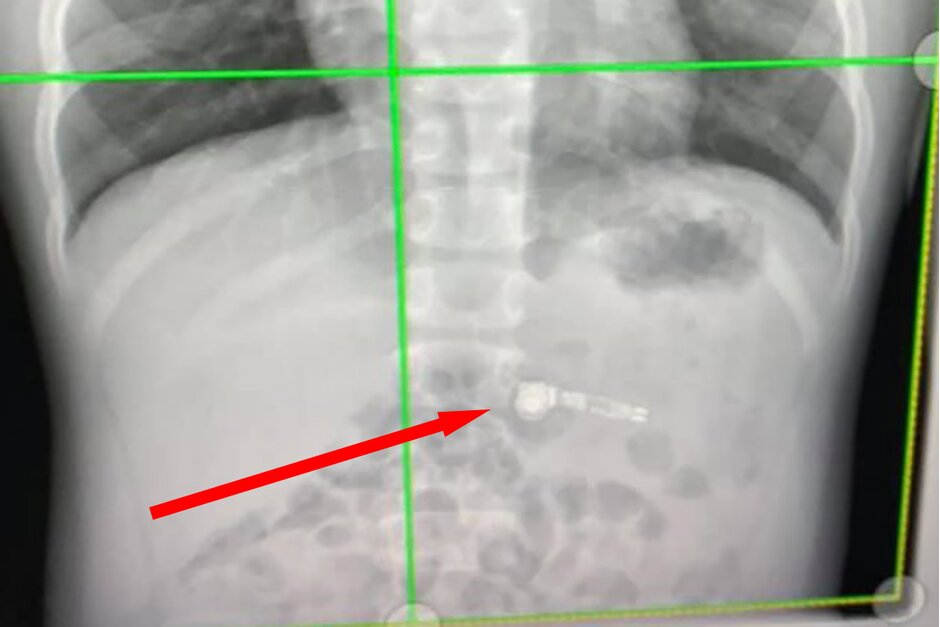

يقول الخبر انه في الرعاية الصحية للأطفال في أتلانتا إغلستون بالولايات المتحدة الامريكية ، كان الأطباء في حيرة من أمرهم ، لكن صورة الأشعة السينية اكتشفت الأجزاء المعدنية في سماعة الايربود وأكدت أن الطفل قد ابتلع السماعة بالفعل.